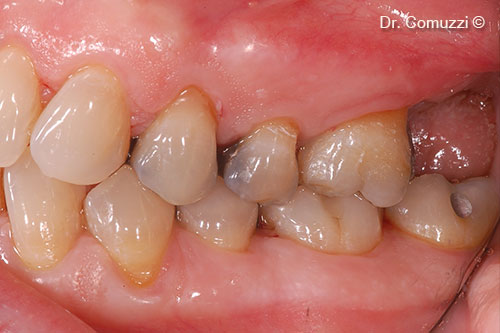

9. Metal try-in